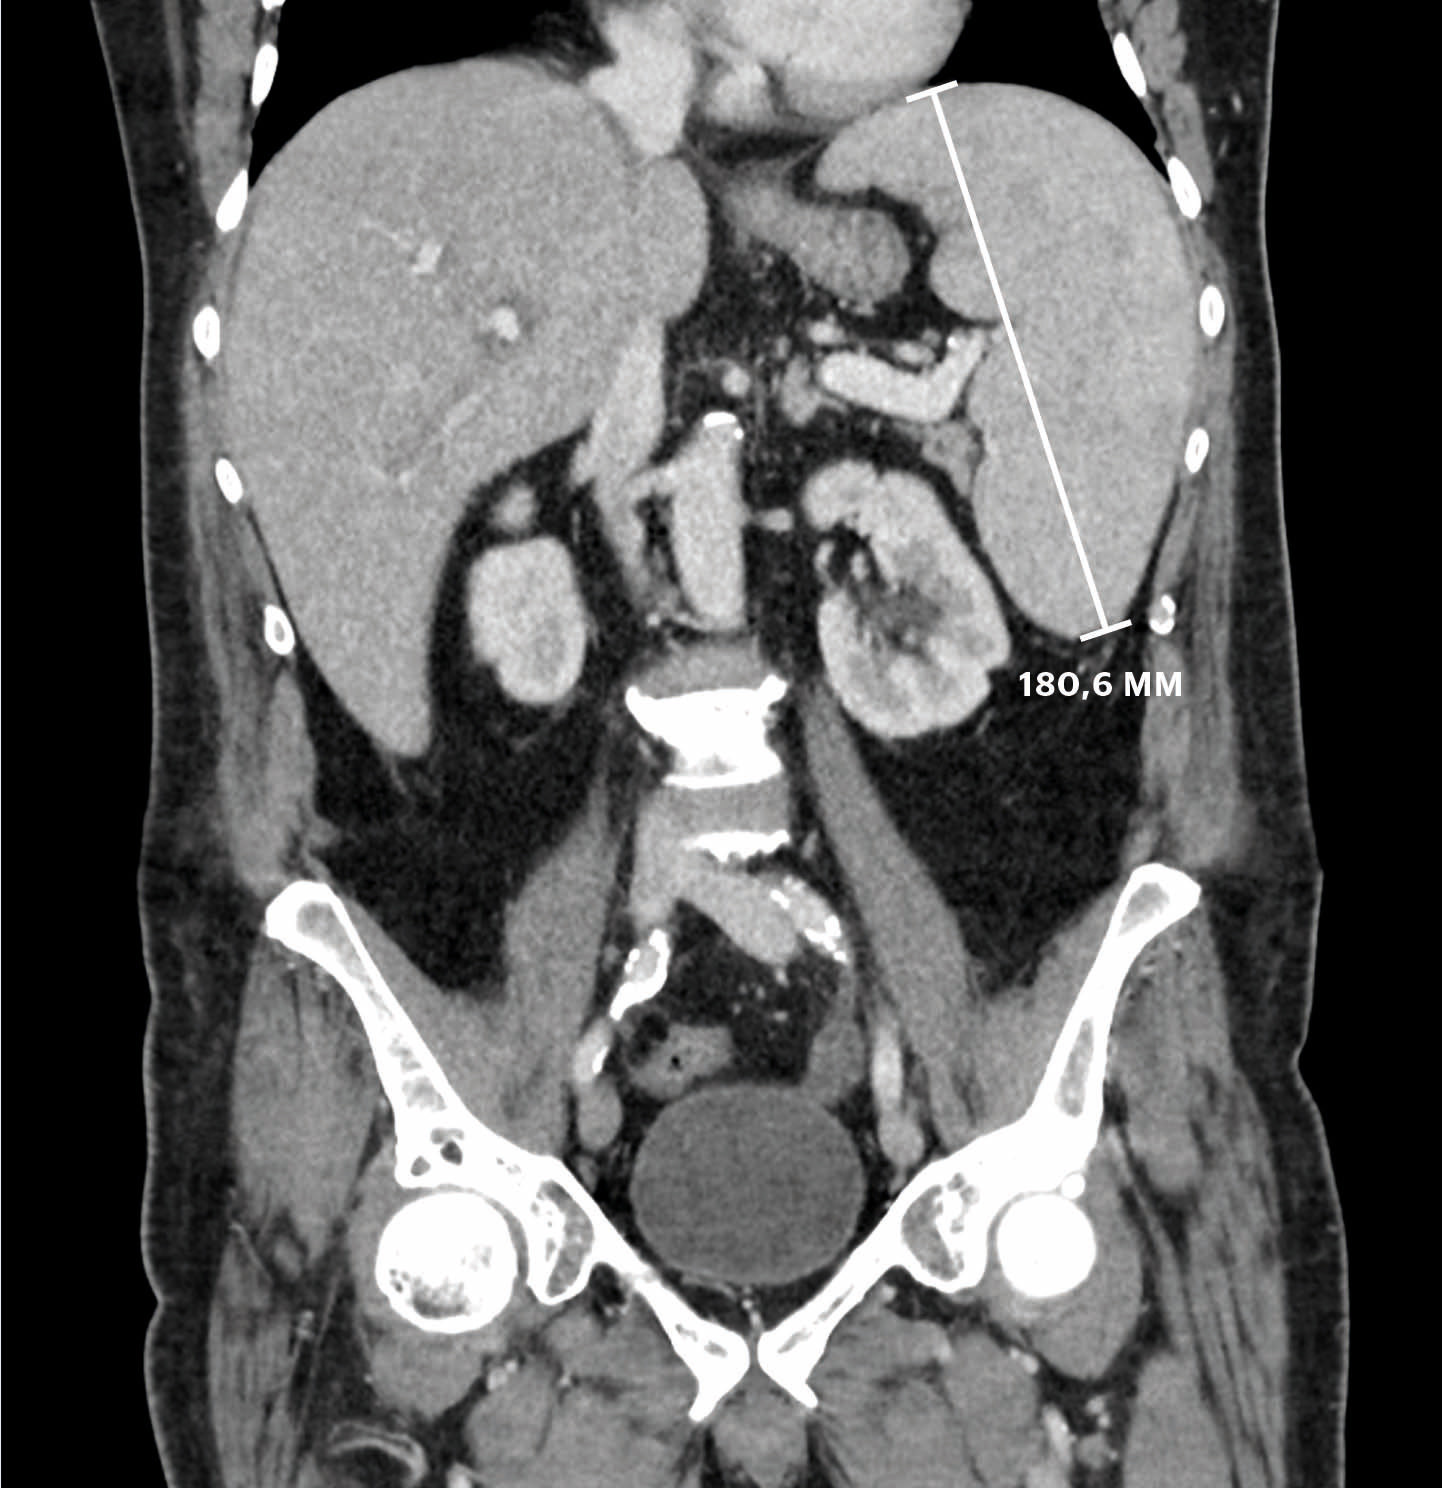

Pasienten hadde pancytopeni. Normale hematologiske verdier ved rutinekontroll to måneder tidligere under pågående behandling med metotreksat gjorde det lite sannsynlig at metotreksat var årsak til pancytopenien. Man mistenkte kreftsykdom, særlig blodkreft. CT thorax på dag 3 viste ingen forstørrede lymfeknuter eller svulst, men lette fibrøse drag i lungene og forstørret milt med aksial diameter på 16,8 cm, som kunne være forenlig med lymfom eller leukemi. Den forhøyde ferritinverdien ble tillagt ferritins egenskap som akuttfasereaktant. Postlege vurderte pneumoni forårsaket av resistente bakterier som mer sannsynlig og endret antibiotikabehandlingen til meropenem 1 g × 3 intravenøst.

Pasienten ble henvist til MR av lever for å lete etter mikroabscesser som kan ses ved systemisk candidiasis. MR av lever dag 12 viste ingen abscesser, men mulig miltinfarkt. For å avklare dette ble CT thorax/abdomen/bekken med kontrastvæske tatt dag 13. Bildene bekreftet miltinfarkt og økende miltstørrelse til 18 cm (figur 1). Leveren var forstørret uten at dette var kommentert i primærbeskrivelsen. Miltinfarkt gav mistanke om endokarditt. Klinisk undersøkelse dag 13 påviste ingen bilyd eller endokardittstigmata. Ved transtorakal ekkokardiografi dag 15 var det ingen holdepunkter for endokarditt. Dag 21 ble antibiotikabehandlingen stoppet for å øke sjansen for positive blodkulturer. For å utelukke infeksjon ble det under oppholdet totalt tatt 28 sett à 4 flasker. Disse hadde ikke oppvekst av verken sopp eller bakterier.